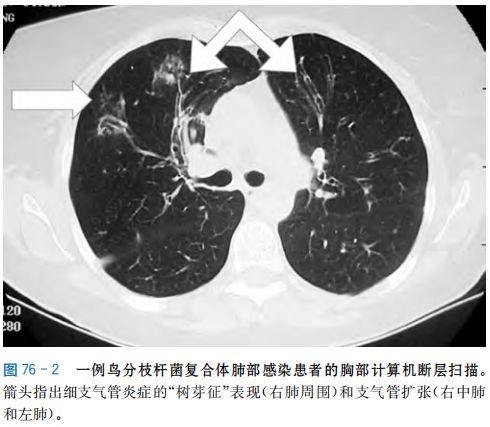

肺mac感染 影响肺部。这是最常见的mac感染类型,主要影响患有肺部疾病的人。 禽分枝杆菌复杂感染的迹象开始缓慢,并随着时间的推移逐渐恶化。 滴鼻组为(6 150 士 照组 0021) Ig cfu/mL尾静脉组为(6 1土0008) 19 固 3 结核分校杆菌标准毒株 H37Rv 不同途径 cfu/mL,对照组肺部无结核分枝杆菌;各感染组与 接种小鼠后肺组织抗酸集色结果(X 40) 对照组比较,差异均有统计学意义(t=3762